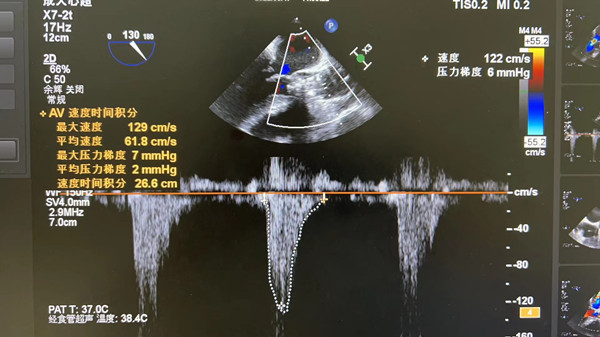

患者张先生,71岁,10余年前因活动后胸闷、气短在外院行心脏超声诊断风湿性心脏联合瓣膜病,建议外科换瓣手术,患者拒绝。1月前活动后气短明显加重,伴夜间端坐呼吸,双下肢水肿,外院给予纠正心衰等治疗,因症状缓解不明显转入我院。行心脏超声提示:主动脉瓣重度狭窄(瓣口面积0.3cm2,瓣口流速629cm/s,平均跨瓣压90mmHg)伴大量反流,二尖瓣轻度狭窄伴中-大量反流,三尖瓣大量反流,肺动脉重度高压,双房扩大,左室增大,心包少-中量积液。胸部CT示两肺间质性改变;两肺支气管炎改变;右肺中叶及左肺上叶慢性炎症;两肺多发肺大泡,左肺下叶肺气肿,双侧胸腔积液。冠脉CTA示冠脉多支病变伴钙化。心血管病院郑强荪院长、韩振华主任等组成的心脏瓣膜团队讨论后认为,患者病程长、心衰症状重,加之冠脉病变严重、肺功能差,外科风险大,经与患者及家属充分沟通各种手术风险及获益,患者及家属同意行TAVR+PCI一站式手术。

在我院心外科裴斐主任医师,麻醉科刘鹏斌主任医师、罗斌主治医师,超声科韩东刚副主任医师、金鑫主治医师,曹春晖护士长领导的护理团队等多学科协助下,韩振华主任、王新宏副主任医师、刘小军主治医师等先为患者行冠脉造影提示右冠近段95%狭窄(图1),先行PCI干预,右冠植入3.0x22mm支架1枚(图2)。后成功为患者植入TAV24mm VitaFlow瓣膜系统,DSA造影显示主动脉瓣位置良好,未见明显瓣周漏(图3),左右冠脉造影正常,术后即刻心脏超声示最大跨瓣流速129cm/s,最大跨瓣压差7mmHg(图4),顺利结束手术。